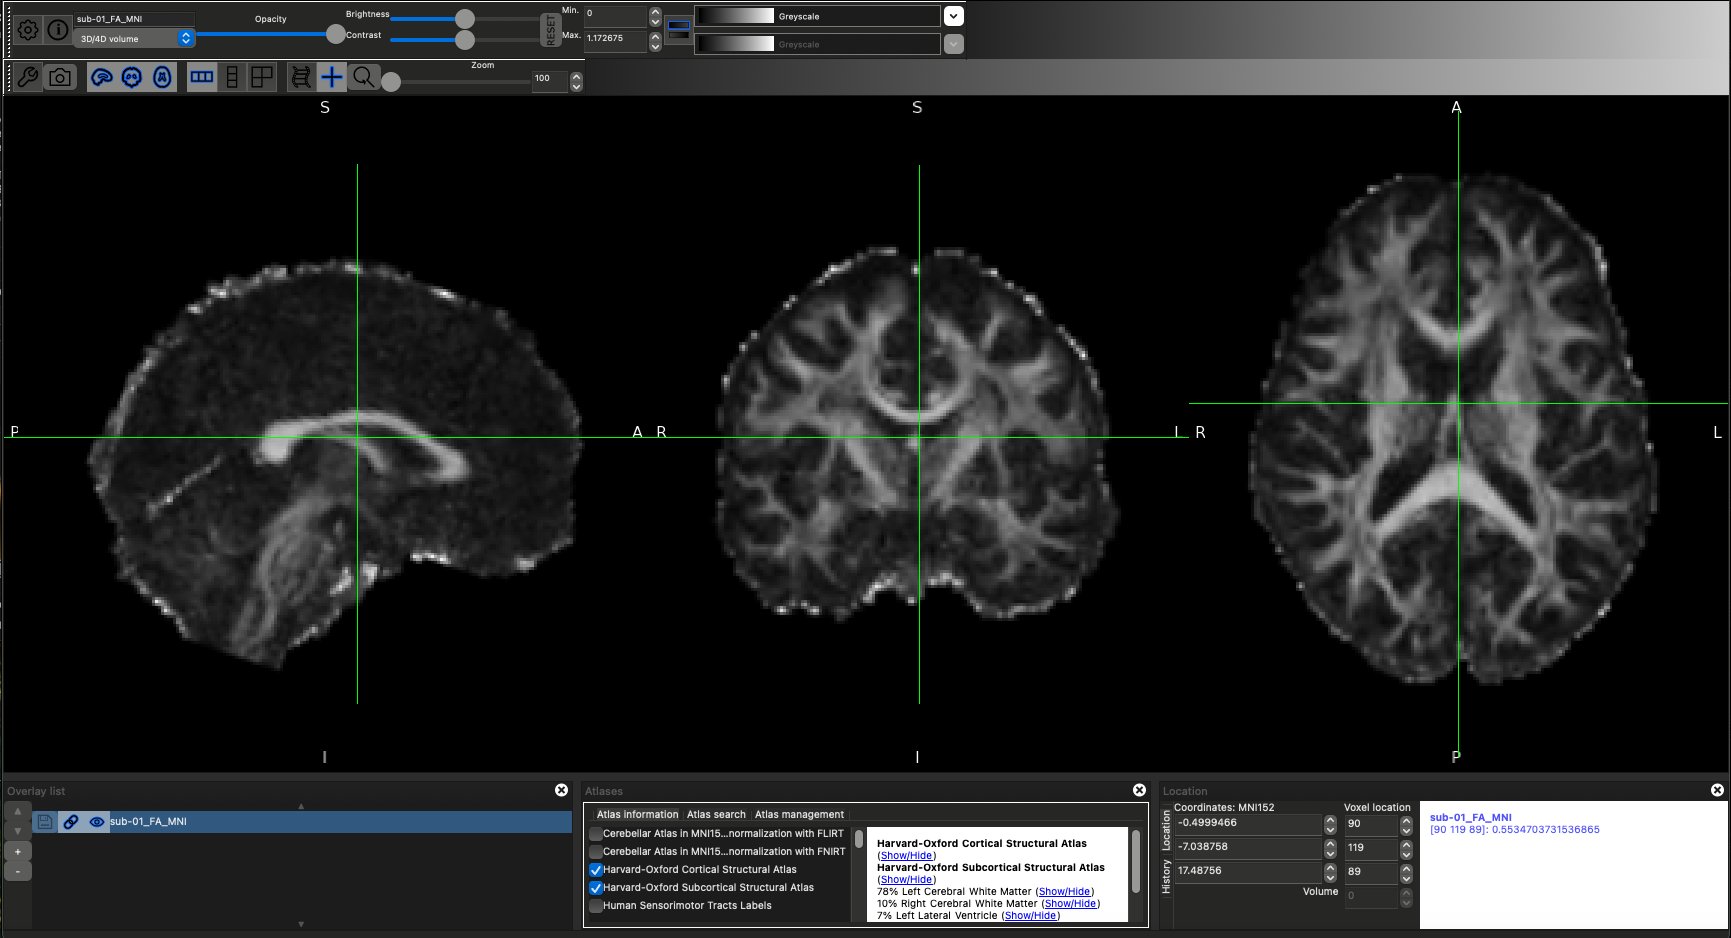

DWI Imaging - ds005874

- Loaded both DWI runs for AP and PA scans (run-01 and run-02), bval and bvec files, as well as acqparam and index files into FSL.

- Ran the BET command to extract the binary brain masks from the raw DWI imaging files

- Preprocessed data by running the

- topup (to correct any magnetic field inhomogeneities) and

- eddy (eddy current induced motion artifacts) commands that would affect downstream analysis.

- For eddy, due to computational constraints, I decided to use 20 subjects out of the 51 subject fMRI cohort (age and sex balanced, with approx 11:9 male female ratio and mean age of 57), with 10 of them being ALS patients and the other 10 being controls.

- dtifit in FSL allowed for conversion of DWI files into Diffusion Tensor Imaging files (DTI), which provided insight onto white matter atrophy for ALS.

- Extracted ROIs from FSLeyes atlases, primarily the JHU White Matter Tractography Atlas and the JHU ICBM-DTI-81 White Matter Labels based on literature coverage of CST regions, the Visual Network, the Salience Network, and the Default Mode Network.

- Regions of significant atrophy in the ALS patients compared to controls were compared to find any differences in connectivity correlating with fMRI connectivity disparities, which may have indicated compensatory networks or significant structural atrophy.

DWI Analysis Results

Diffusion Weighted Imaging (DWI) and Diffusion Tensor Imaging (DTI) are two specialized MRI methods that detect water diffusivity over a period of time. This equips researchers with the ability to test potential structural integrity in the brains of ALS patients, which is pivotal in understanding more about the disease. The DWI analysis consisted of 10 ALS patients and 10 Controls, age and sex matched so that the mean age was roughly the same as the fMRI cohort. As for sex, I kept sex relatively equal as well (11:9 male to female ratio) to ensure that sex wasnt a major confounder in any structural disparities. The results of DWI are shown below. Specific ROIs included the corticospinal tract (CST), the Corpus Callosum (CC), the Cingulum Bundle (CING), and the Superior Longitudinal Fasciculus (SLF). Only the CST was extracted bilateraly due to its presence on both hemispheres of the brain, whereas the Corpus Callosum, a midline structure, came as is.

Diffusion-weighted imaging (DWI) revealed multiple structural alterations consistent within the known ALS pathology. For instance, corticospinal tract (CST) fractional anisotropy (FA) was observed to be slightly lower in ALS participants compared to controls, indicating possible reduced white matter integrity within the primary motor pathway leading to the spinal areas. Conversely, mean diffusivity (MD) within the CST was elevated in ALS patients relative to controls, suggesting increased water diffusion associated with axonal degeneration or myelin disruption. Together, these complementary diffusion metrics support the presence of structural degeneration along the motor pathways that are characteristically affected in ALS.

Beyond the corticospinal tract, additional white matter tracts demonstrated patterns that may reflect extra-motor involvement in ALS. Moderate differences were observed within the corpus callosum and superior longitudinal fasciculus, both of which showed trends toward reduced FA and increased MD in ALS participants. These findings may indicate broader disruptions in interhemispheric communication and frontoparietal connectivity. In contrast, the cingulum bundle demonstrated comparatively smaller differences between groups, though subtle alterations were still present. Collectively, these results suggest that while degeneration is most pronounced in motor pathways such as the CST, ALS-related microstructural changes may extend into association and network-supporting tracts, providing structural context for the functional connectivity alterations observed in the fMRI analyses.

Figures - DWI data

DTI scan overlayed with Harvard-Oxford atlases.